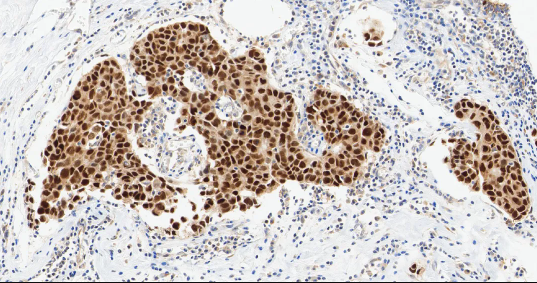

Ki-67

Ki-67——细胞增殖相关的标志性蛋白。

• 定位:细胞核

• 功能:Ki-67 是重要的细胞增殖标志物。它标记处于活跃细胞周期 (G1、S、G2和 M 期) 的细胞核,其表达指数 (阳性细胞百分比) 直接反映肿瘤的增殖活性和生长速度。

图 7. Ki-67 在整个细胞周期中的定位。

KI-67 是评估癌细胞增殖活性的通用标志物,与所有需评估增殖活性的癌症均相关。在乳腺癌中,它是区分 Luminal A 型和 B 型亚型的关键参数之一。

图 8. 人乳腺癌组织的 Ki67 免疫组化分析。